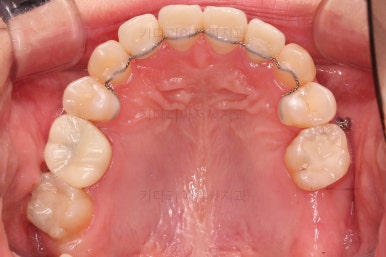

덧니를 개선하기 위해서 추가적으로 작은 어금니를 발치했고요.

이 때 발치하게 된 치아는 가장 약한 치아, 치료가 많이 되어있거나 치료가 필요한 치아 위주로 선택하게 됩니다.

치열은 매우 가지런해졌고요.

추후에 발치 공간을 모아나가야 합니다.

윗니 앞니는 급한대로 신경치료 부터 진행했고, 최종 심미보철은 교정 후 미루었습니다.

공간을 줄여나가고 순차적으로 충치치료도 마무리 해갑니다.